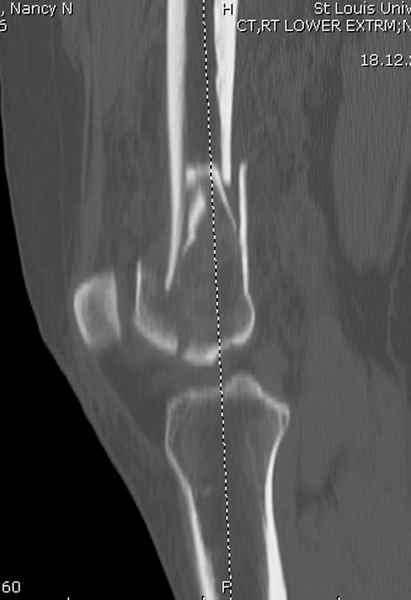

Мы бы не стали открывать, такие переломы срастаются, хотя бы и с краевым дефектом. То есть если удалять стержень потом, то сильно попозже обычного. В приложении пример. Сразу после операции и через 11 мес. Понятное дело, пациент к тому времени давно и не хромал, и функция колена была полная.

При наличии различных имплантов, любые варианты: слева (полу) открытым - мининвазивным, а справа закрытым интрамедуллярным методом, его считаем более чем приемлемым для фиксации данных переломов.

Проксимальная и дистальная блокировка, независимо от техники введения штифта, ретроградно или антеградно, гарантирует сращение сегментарных переломов бедра без укорочения. Штифты диаметром 12 мм с блокировкой сверху и вниз двумя шурупами выдерживают вес 75 кг больного, что позволяет раннюю профилактику контрактур.